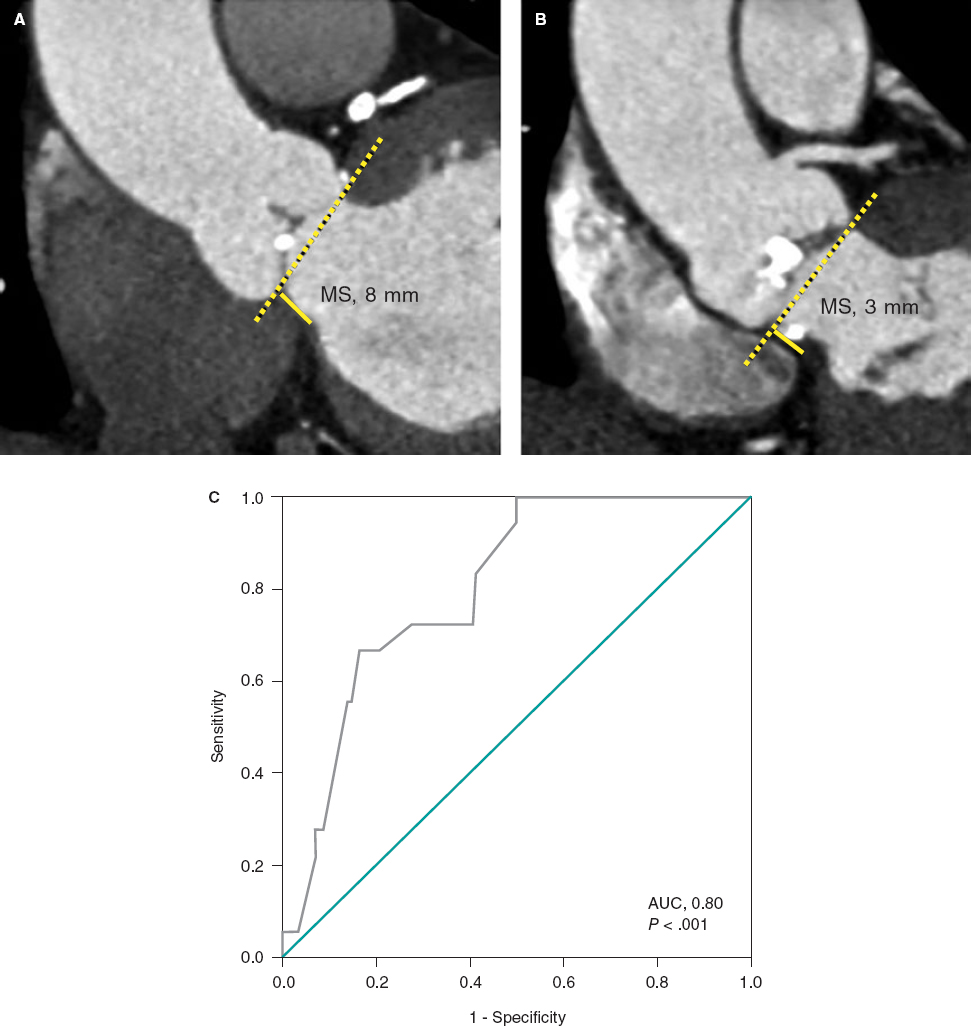

An 84-year-old female with severe aortic stenosis and previous non-disabling stroke was referred to undergo transcatheter aortic valve replacement (TAVR). The 3D computed tomography performed revealed the presence of a type 9 aortic arch with severe tortuosity (figure 1A). It was decided to protect the supra-aortic branches with suitable diameters to be able to use the Sentinel Cerebral Protection System (Boston Scientific, Marlborough, MA, United States). Manipulation length in the left common carotid artery (LCCA) was of, at least, 8 cm which is the distance between the proximal filter and the Sentinel distal edge. Figure 1B: yellow arrow: brachiocephalic trunk, 12 mm-diameter. White arrow: LCCA, 7 mm-diameter. This cerebral protection device (CPD) has a proximal filter for brachiocephalic trunk diameters between 9.0 mm and 15 mm and a distal filter for LCCA diameters between 6.5 mm and 10 mm. The angiography of the aortic arch is shown on figure 1C. This dual-system-filter basket was tried unsuccessfuly over a 0.014 in guidewire despite the use of an articulating sheath (figure 1D-F). After several attempts, a multipurpose catheter was used to engage the LCCA (figure 1G). Using a 300 cm 0.014 in guidewire, the multipurpose catheter was exchanged for the CPD which allowed its suitable deployment (figures 1H,I). The TAVR was performed successfully and the CPD was retrieved (video 1 of the supplementary data). Informed consent was obtained from the patient.

Figure 1.

The major concern is how to balance the risk of stroke after TAVR and the risk of manipulation with guidewires/catheters in supra-aortic arteries. Thus, the rigorous study of the computed tomography scan is the key factor for strategic planning purposes. This was an alternative approach to achieve the placement of a Sentinel device using a multipurpose catheter in a complex aortic arch.